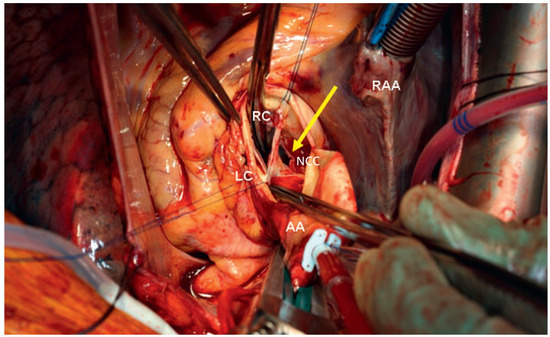

Aortic Valve Rupture Due to a Motorcycle Accident

by Daniela Vocke, Igal Moarof, Peter Matt and Pablo Anabitarte

Cardiovasc. Med. 2011, 14(6), 192; https://doi.org/10.4414/cvm.2011.01597 - 29 Jun 2011

Viewed by 93

Abstract

A 62-year-old male patient was admitted as a result of a motorcycle accident [...] Full article